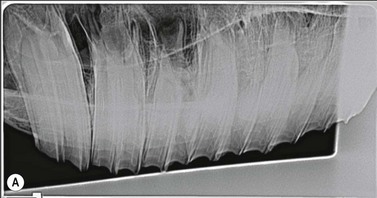

image image image

Fig. 13.36 Polydontia. Supernumerary maxillary cheek teeth (Triadan12s) are the most common supernumerary cheek teeth in horses. The 12 is usually markedly overgrown as in (A) but may be unerupted as in (B) if there is inadequate space (overcrowding). Note the abnormal shape of the apical area of the 112. (C) An example of overgrown bilateral supernumerary mandibular 12s.